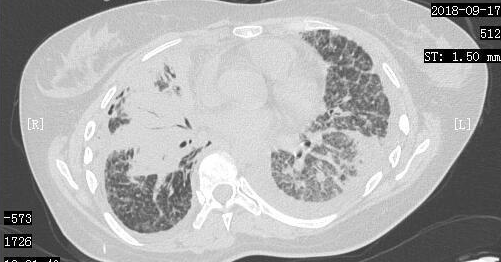

在经历了短暂的绝望后,小周一家决定齐心协力,积极进行抗癌治疗。2018年9月7日,小周进行了胸腔穿刺抽液,同时进行了胸腔灌注化疗。2018年9月14日,小周来到了我们医院进行治疗,复查了胸部CT,当时的胸部CT显示肺部一般情况非常差。

2018-9-17日CT